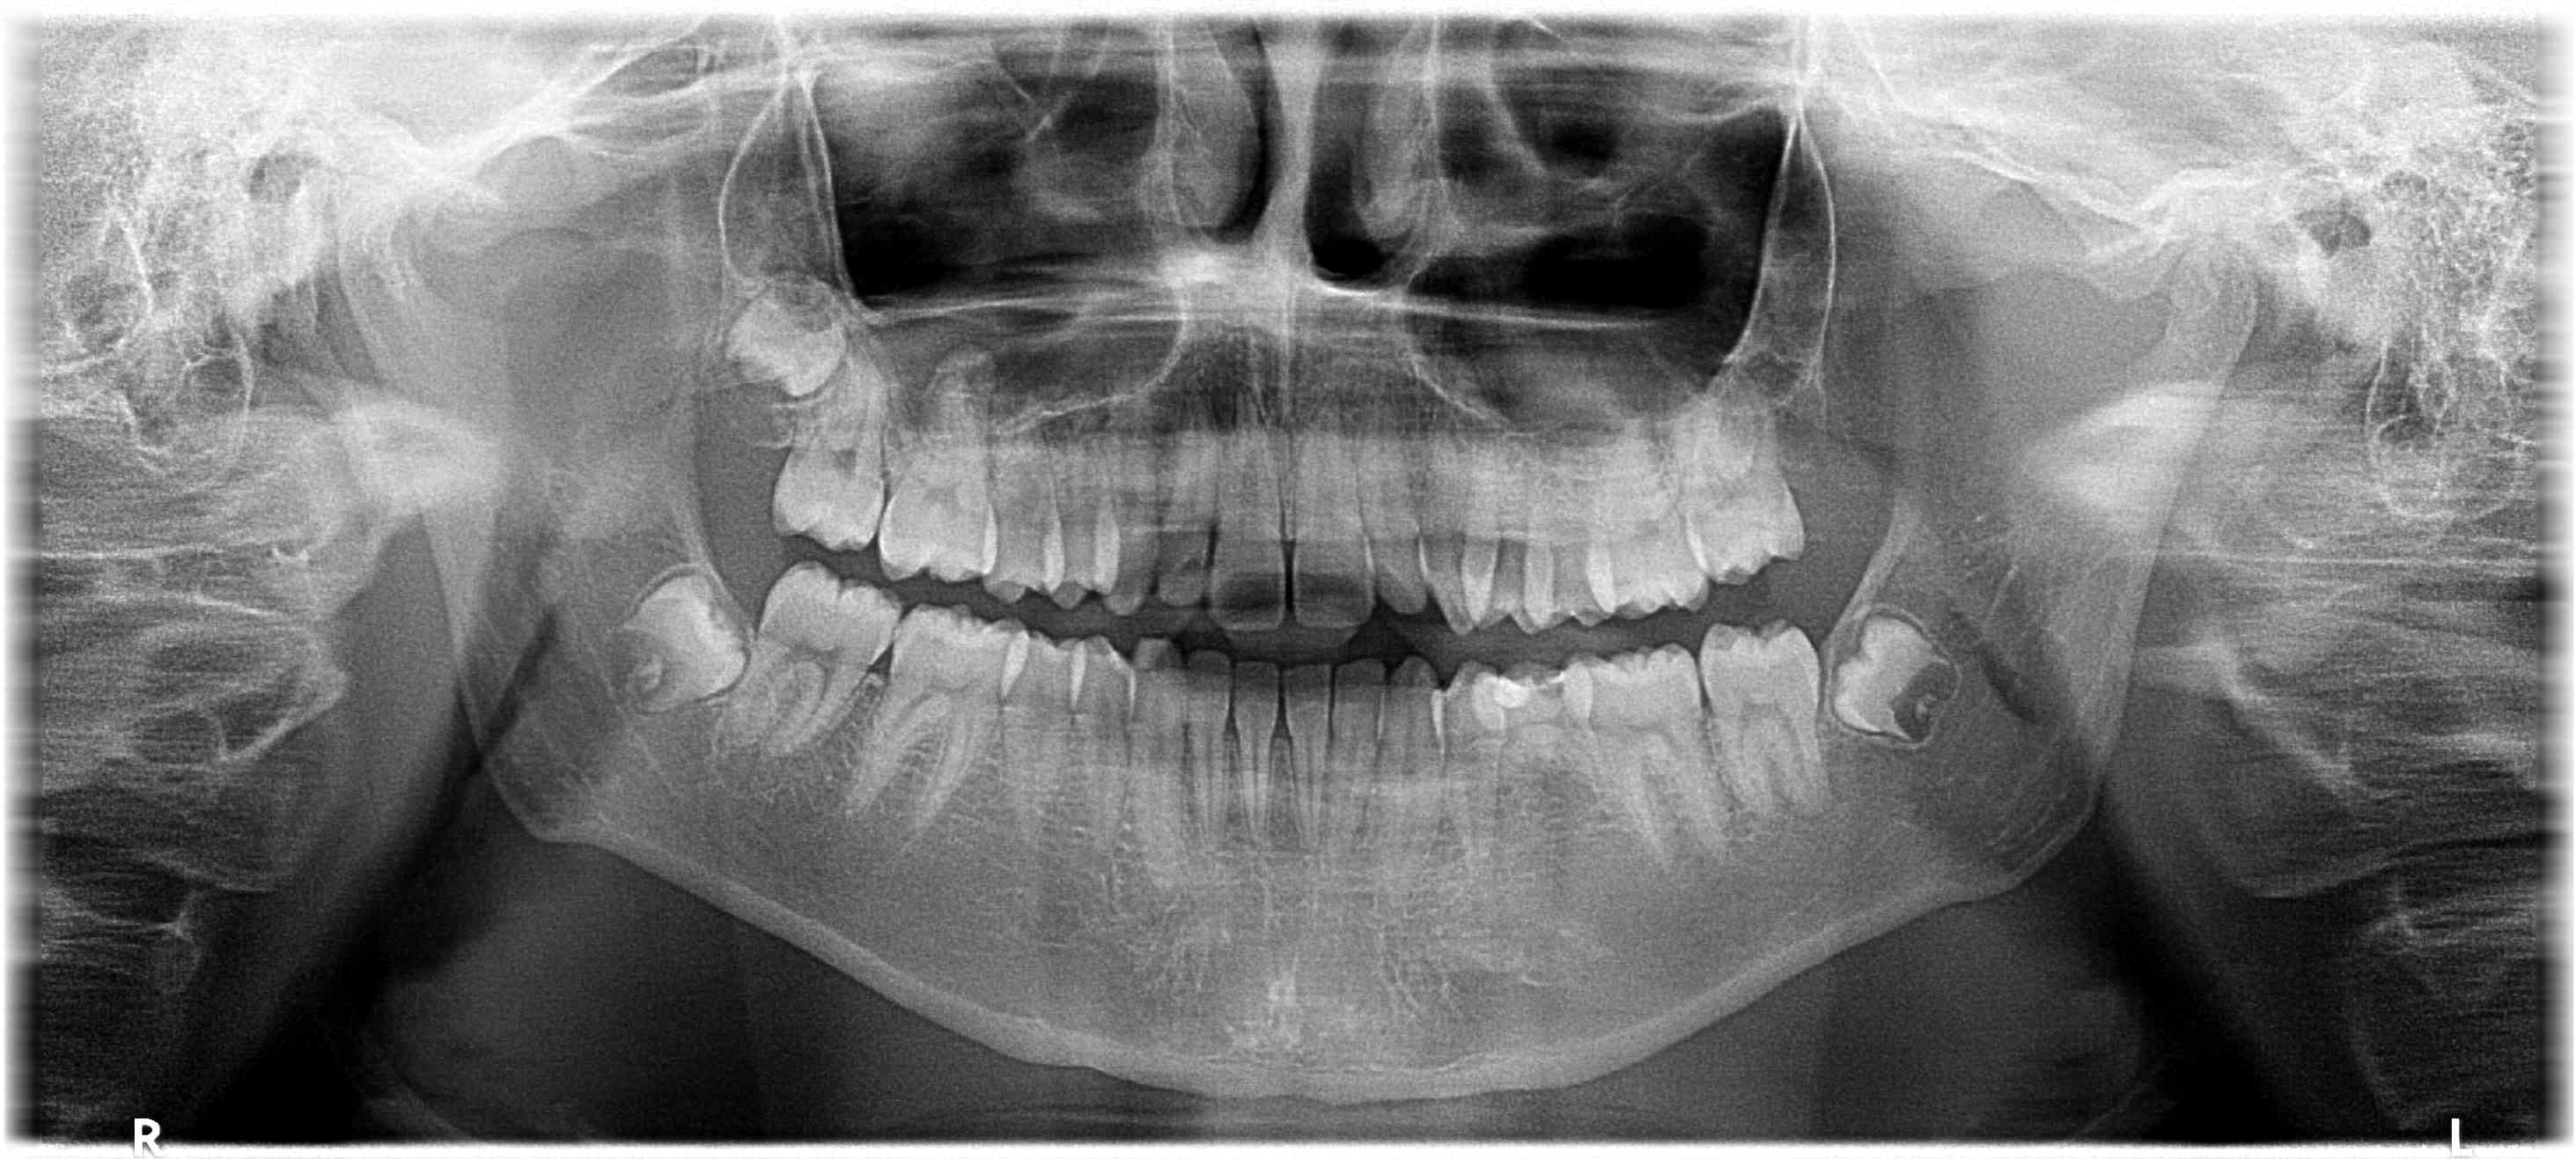

Que feriez-vous pour résoudre un claquement fort chez un ado de 17 ans, apparu suite à un rire trop fort, semble-t-il, sans atcd d'ortho, accident (...), DDS incluses et asymptomatiques, des 7 en évolutions ?

La pano

Je regarderais bien la 37 .

et vu qu' il n a pas eu de soins j éliminerais la 1ere proposition . en effet , il est peut etre tout simplement un peu tordu , (il lui reste une dent de lait , non ?) avec certainement un ou des occlusions croisées mais peu importe , il peut être bien calé comme ça sans possibilité de compression .